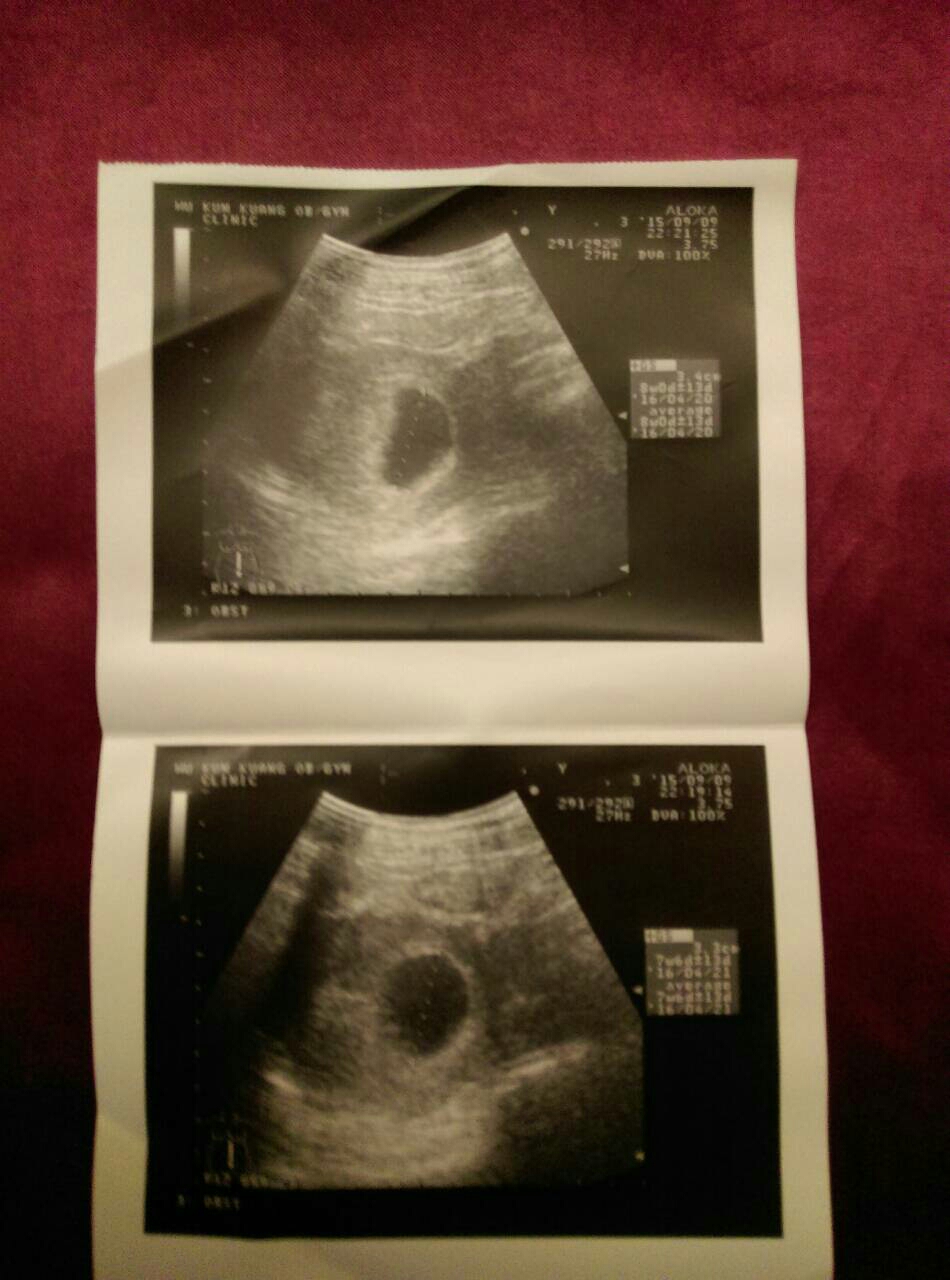

裡面沒東西啊⋯⋯⋯...(恕刪)

七週的超音波應該要有胚胎了

這個看起來比較像剛著床不是七週的

別難過了, 那"超音波"是假的, 你沒有殺害一個生命, 好嗎?!